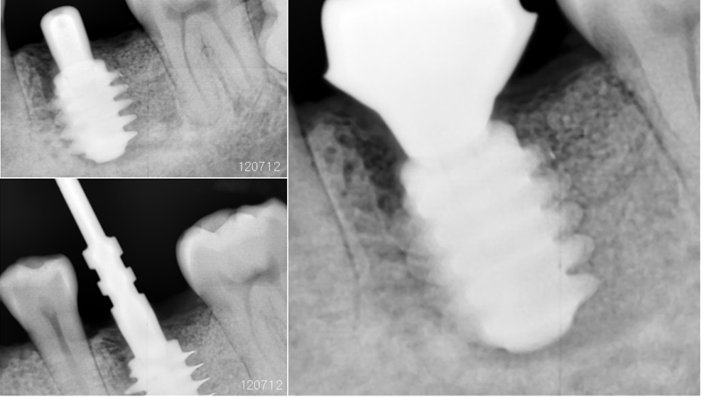

Clinical case: Bone filling into the bottom of deepest thread at 8.0mm AnyRidge fixture

- Courtesy of Dr. Kwang Bum Park -

Keywords

AnyRidge, Knifethread ,extraction socket, ,initial stability ,Allograft, ,osseointegratio ,Dr. Kwang Bum Park, , Mandibular, Single replacement, AnyRidge, Mega-oss,

Products used

Implant system-AnyRidge, Regeneration-Mega-Oss